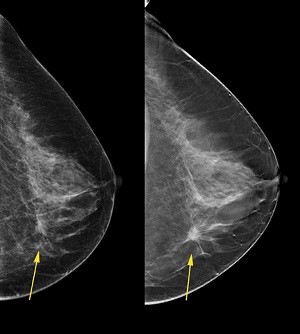

عکس ماموگرافی سالم

عکس ماموگرافی سالم؛ ماموگرافی چیست؟

ماموگرافی یک عکس برداری با اشعه ایکس از سینه ها است. این امکان را فراهم می کند تا با استفاده از اشعه ایکس تصاویری از داخل سینه به دست آورید و در نتیجه هر گونه ناهنجاری را تشخیص دهید. توسط رادیولوژیست انجام می شود. دو عکس اشعه ایکس از هر پستان گرفته می شود، یکی از جلو و دیگری مایل، که امکان مقایسه دو طرف هر سینه را فراهم می کند.

ماموگرافی در حالت ایستاده انجام می شود. سینه بین یک نگهدارنده کاست و یک دستگاه فشرده سازی قرار می گیرد. در اکثریت قریب به اتفاق موارد، دو تصویر برای هر پستان گرفته می شود: یکی از جلو و دیگری با فرورفتگی مایل، یعنی در مجموع 4 تصویر.